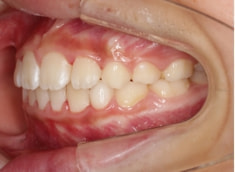

治療中